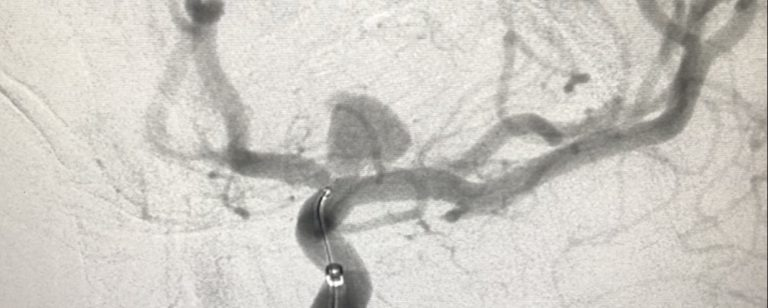

Калифорнийская компания Cerus Endovascular объявила о первой в истории роботизированной установке внутричерепного имплантата. Знаковая операция заняла всего 18 минут, включая обеспечение оперативного доступа. Её провёл нейрохирург Нитин Данге в Мемориальной больнице им. короля Эдуарда в Мумбаи, Индия. Доктор Данге использовал микрохриругическое устройство Xcath — медицинского робота, созданного одноимённой техасской фирмой. Он применялся для установки внутрисосудистого протеза Contour — новинки от Cerus Endovascular, останавливающей растяжение и последующее разрушение аневризмы. Contour представляет собой объёмную сетку из инертного материала, которая закрепляется на штифт-проводник и может менять форму, расширяясь по команде хирурга. Её отличие от подобных протезов состоит в том, что Contour изначально создан для установки с помощью робота Xcath. Это обеспечивает сверхточное позиционирование и надёжную фиксацию протеза. Более того, при необходимости Contour можно снова сложи

Он применялся для установки внутрисосудистого протеза Contour — новинки от Cerus Endovascular, останавливающей растяжение и последующее разрушение аневризмы.

Contour представляет собой объёмную сетку из инертного материала, которая закрепляется на штифт-проводник и может менять форму, расширяясь по команде хирурга.

Её отличие от подобных протезов состоит в том, что Contour изначально создан для установки с помощью робота Xcath. Это обеспечивает сверхточное позиционирование и надёжную фиксацию протеза.

Более того, при необходимости Contour можно снова сложить, передвинуть и установить повторно даже в проблемных местах, вроде точки бифуркации.